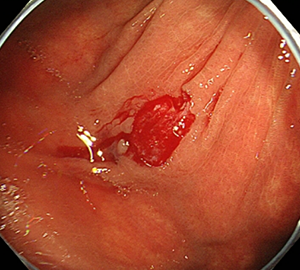

コールドスネアポリペクトミー(CSP)

合併症の非常に少ない優れた治療法であることから、近年大腸ポリープの外来切除法として急速に施行件数が増えてきています。当院ではこのコールドスネアポリペクトミーを主体としたポリープ切除を行っています。

| 1:ポリープを見つけます。 | 2:狭帯域光画像併用拡大観察で詳細に観察します。 | |

| 3:病変をスネアに通します。 | 4:周囲の正常粘膜をしっかり入れながら、病変を絞扼していき... | |

| 5:切除します。切除検体は吸引回収し病理検査を行います。 | 6:切除後に洗浄・観察して、病変の遺残ががないことを確認します。 |